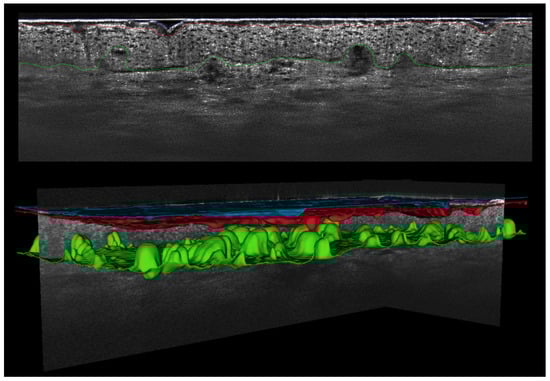

The chosen 3D stacks were analyzed with artificial intelligence models developed by Damae Medical (Paris, France). One model was trained for skin layer segmentation, the other model for follicle detection. The segmentation of the skin layers and identification of stratum corneum, epidermis, and dermis were realized through the application of a 2D U-Net model to the LC-OCT stacks. The boundaries of the different skin layers were defined using the interface between two segmented areas; for example, the detection of the DEJ was realized using the pixel boundary between the epidermis and dermis. The AI model was trained on a big and diverse dataset, including acquisitions of healthy skin from different body parts and different extent in the undulation of the DEJ, actinic keratoses, and inflammatory dermatoses like atopic dermatitis and psoriasis. To ensure the highest level of accuracy, all segmentations underwent a meticulous validation process. This involved a comprehensive manual review conducted by a skilled operator, who carefully examined and verified each segmentation output by the model. We used the same U-Net model as described in detail elsewhere [22,28,29,30,31,32,33,34,35,36], especially that by Chauvel-Picard et al. A few studies [22,28,29,30,31,32,33,34,35,36] have already shown the applicability of this U-Net AI model in the evaluation of healthy skin, actinic keratoses, atopic dermatitis, and also in the evaluation of plaque psoriasis.

The segmentation of the skin layers and detection of hair follicles was visually supervised by an expert team to ensure validated results. All 3D stacks with a variation of more than 30% between manually and AI model-generated measurements were reviewed by an expert team to detect possible reasons for differences or wrong measurements. The number of pixels between the blue and red line (see Figure 2 and Figure 3) divided by the number of pixels corresponding to the region of interest was used for calculating the SC thickness (SCT). The result in microns was obtained with the pixel–micron equivalence. The same procedure was used for the ET, calculating the number of pixels between the red and green line and summing up the SCT. DEJ undulation was quantified as the ratio of the DEJ contour length to the straight-line length of the analyzed area in percent. In acquisitions without visible DEJ, because of excessive acanthosis, the AI model placed the green line at the bottom of the stack. For each parameter, the area detected as a follicle by the follicle detection model was excluded from the calculation in order to prevent a bias of the skin layer measurements.

Figure 3.

Three-dimensional (3D) line-field confocal optical coherence tomography (vertical image size: 1.2 mm × 0.4 mm; 3D image size: 1.2 × 0.5 × 0.5 mm3) stack with reconstruction of the artificial intelligence (AI) model-generated segmentation of skin layers (blue = skin surface, red = boundary between stratum corneum and stratum granulosum, green = dermo-epidermal junction).